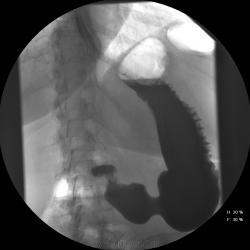

Женищина 49 лет, повышенного питания, обратилась с жалобами на потерю аппетита, жжение после чуть острой пищи, отрыжку с неприятным запахом, иногда темный стул, несколько похудела. Данные жалобы с сентебря-октября. Никуда не обращалась, коррегировала питанием. В последнее время стало хуже, обратилась...

Привратник удлиннен и ригиден, такое бывает при раке. Рек. ЭГДС.

Вы правы. я несколько недорасказал. женщина пришла уже с фгдс - инфильтративно-язвенный процесс в выходном отеде желудка у привратника по малой кривизне с переходом на переднюю стенку. так что прицельно смотрел этот отдел. перистальтка была ослаблена, краевой дефект в препилорической зоне по малой кривизне, передней стенке, кажущееся удлинение привратника, нависание основания луковицы - вообщем как в книжке. эвакуация было не изменена. написал рак выходного отдела желудка. вчера пришла гистология - высокодиф-я аденокарцинома. вот такая история.

Пока, касаясь только луковицы, но не препилорического отдела. "Ниши" в луковице есть, и они нуждаются в объяснении.

Конечно, в пилорическом канале уже растет, и "это" растет, уже и препилорической части и в луковице 12-ти перстной кишки.